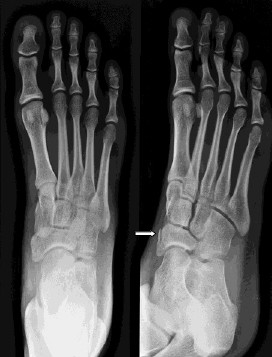

TAG: fraktur tulang

Beranda / Tag / fraktur tulang

Ada 10 Artikel yang mempunyai tag "Fraktur Tulang"